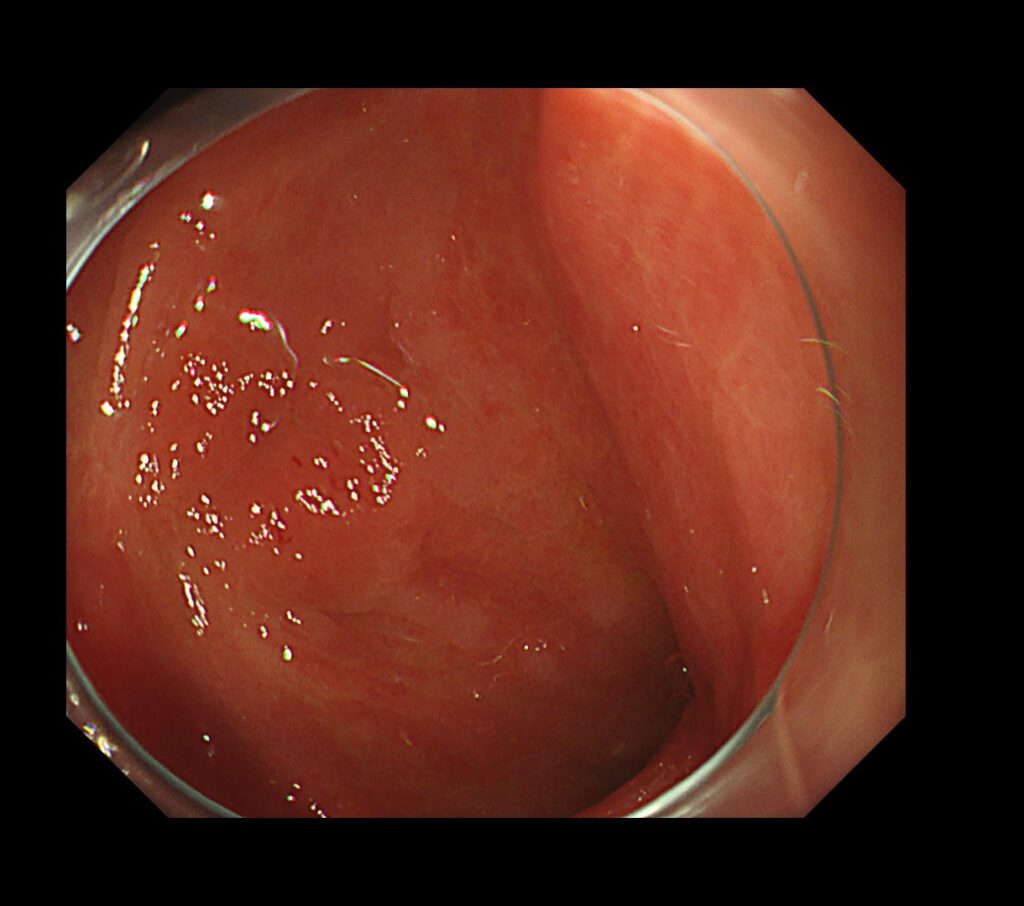

前庭部前壁に易出血領域を認めます。